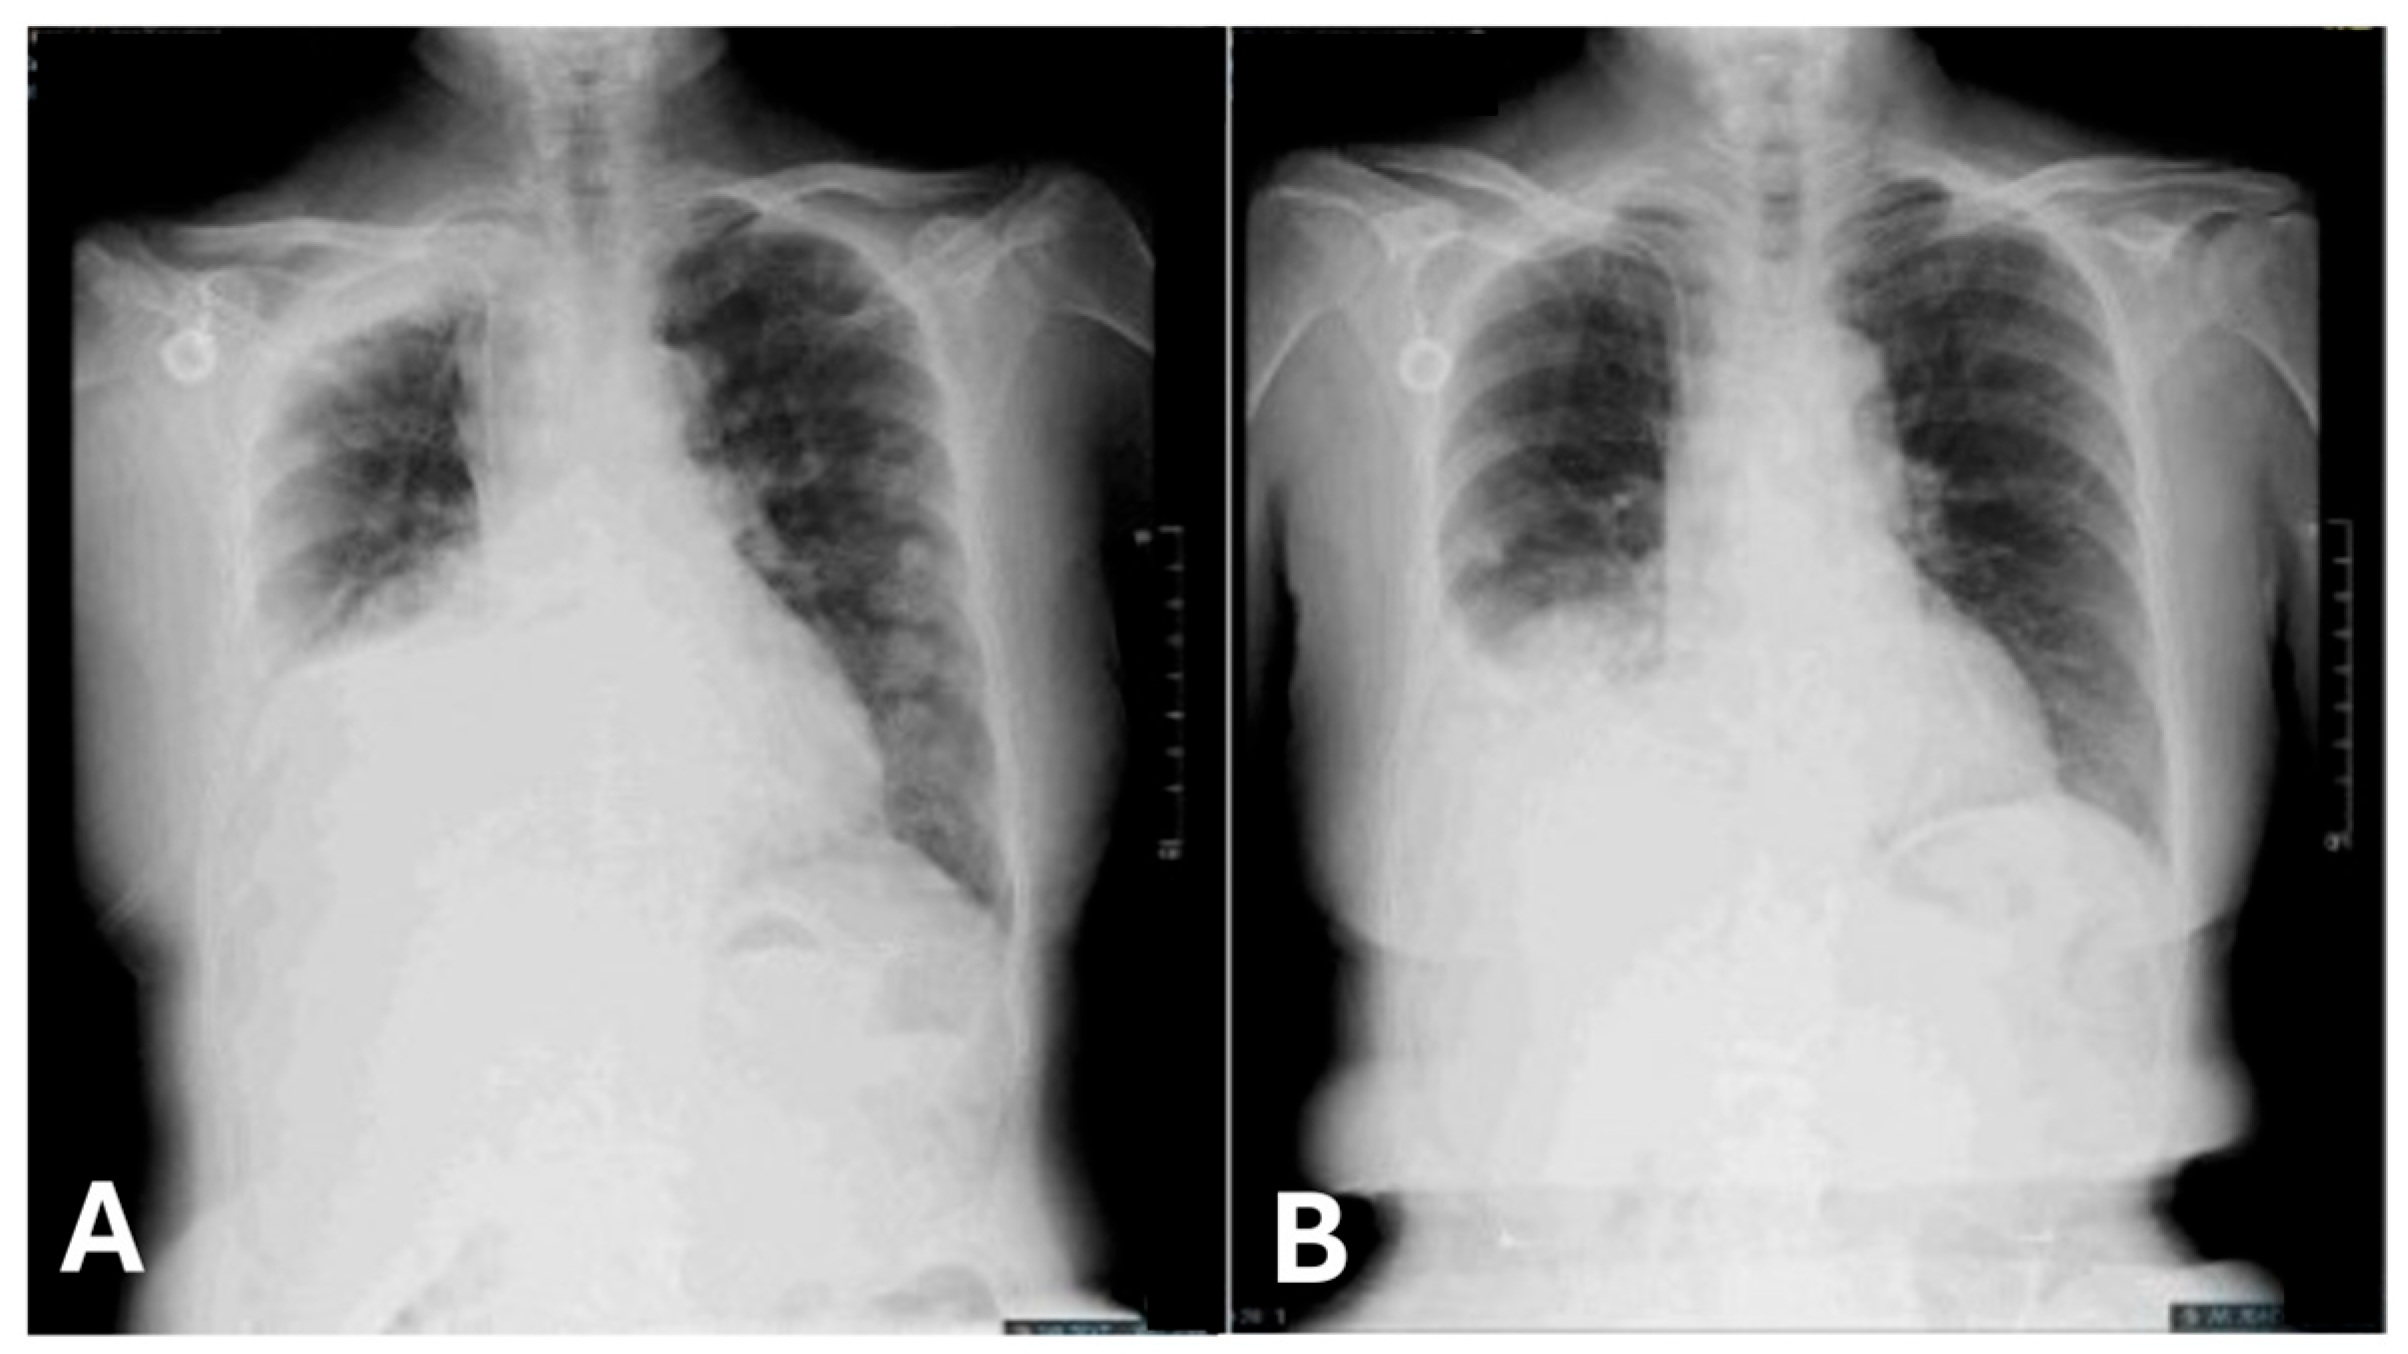

2. Case Presentation